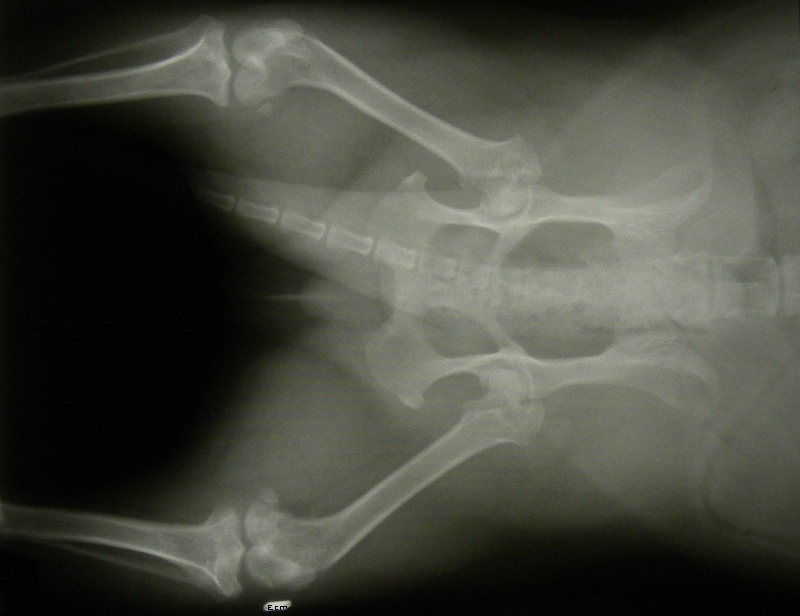

Xray, March 8th 2011.

back.